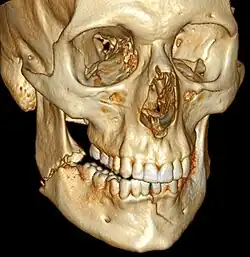

| 3D computed tomographic image of a mandible fracture in two places. One is a displaced right angle fracture and the other is a left parasymphyseal fracture. | |

Computed tomography

Computed tomography is the most sensitive and specific of the imaging techniques. The facial bones can be visualized as slices through the skeletal in either the axial, coronal or sagittal planes. Images can be reconstructed into a 3-dimensional view, to give a better sense of the displacement of various fragments. 3D reconstruction, however, can mask smaller fractures owing to volume averaging, scatter artifact and surrounding structures simply blocking the view of underlying areas.

3D CT reconstruction of mandible fracture, white arrow marks fracture, red arrow marks moderate displacement and open bite -